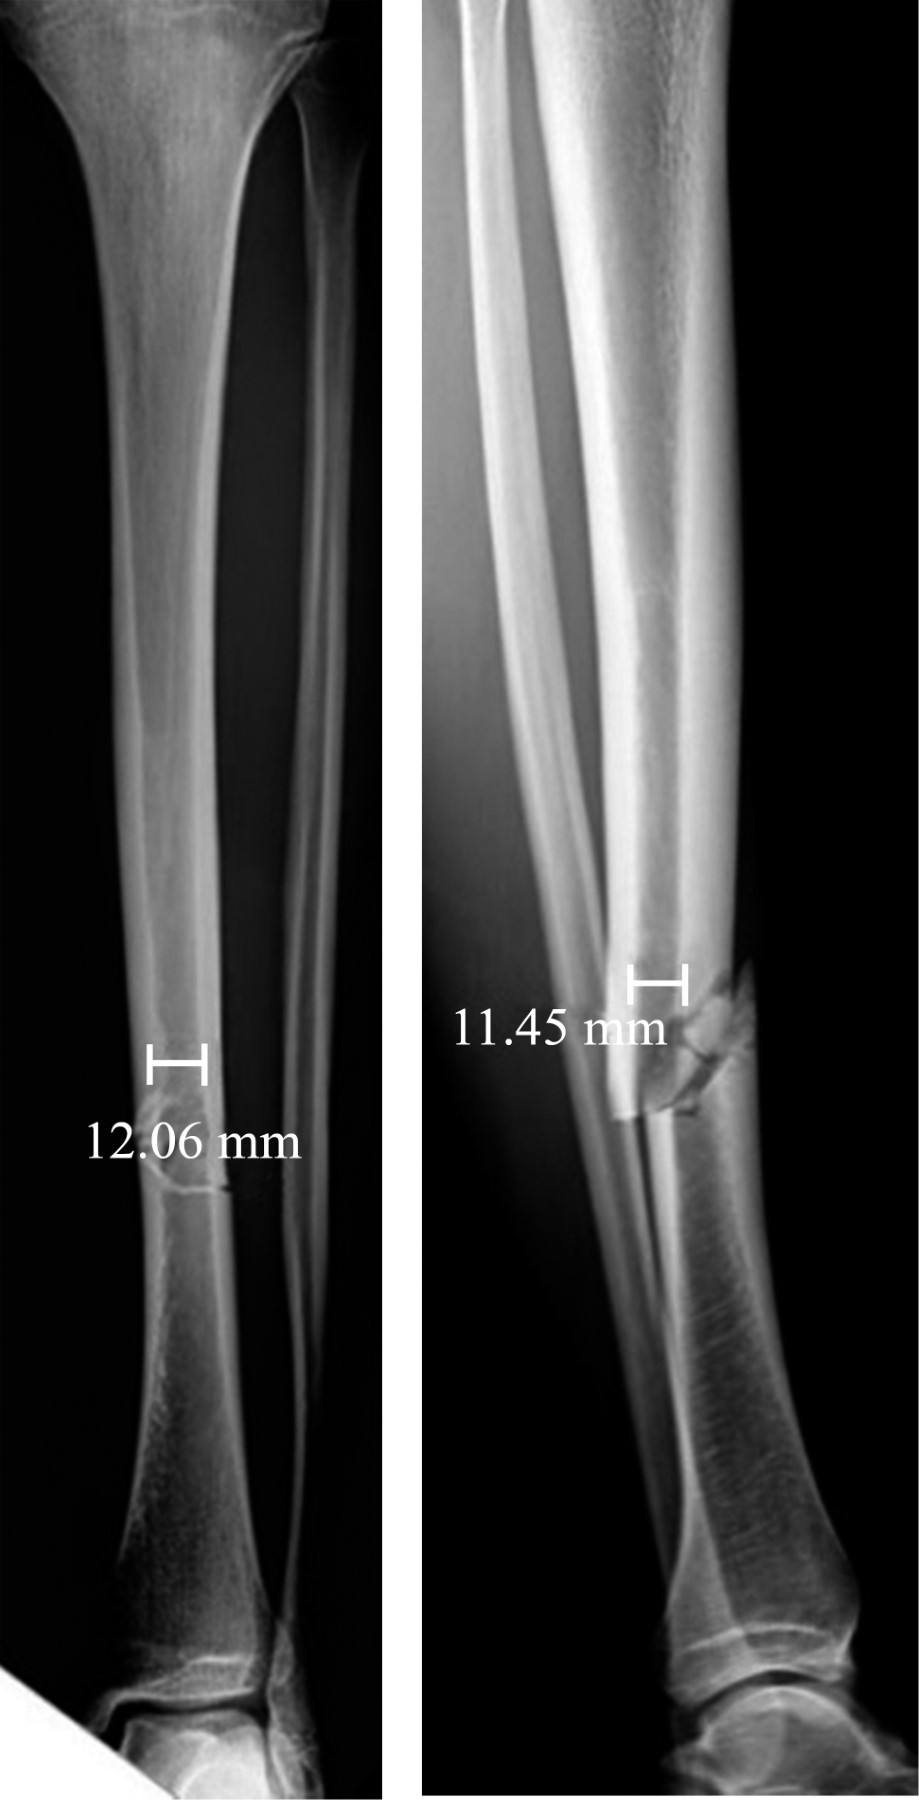

El análisis radiográfico fue realizado utilizando las proyecciones anteroposterior (AP) y lateral (L) de pierna. Con las radiografías del ingreso catalogamos las fracturas según la clasificación OTA/AO. Para determinar el diámetro del canal medular y evitar un sesgo de precisión utilizamos el software digital Synapse (Fujifilm Corporation) de nuestro centro. Dichas mediciones se realizaron en ambas proyecciones radiográficas (AP y L) a nivel del istmo en las radiografías de la lesión (Figura 1). Estas mediciones se realizaron en dos oportunidades (con un intervalo de tres meses) por dos observadores independientes y las diferencias se resolvieron por consenso junto al cirujano más experimentado. El diámetro del clavo se obtuvo de los registros del protocolo quirúrgico.

La discrepancia canal-clavo se obtuvo del valor resultante de la diferencia entre el diámetro del canal tibial y el diámetro del clavo. Por otra parte, la razón entre el diámetro del clavo sobre el diámetro del canal tibial se consideró como el índice clavo-canal, de acuerdo con lo establecido por Donegan y colaboradores.16 Además se registró el número de cerrojos utilizados tanto a proximal como a distal de la fractura.

Figura 1